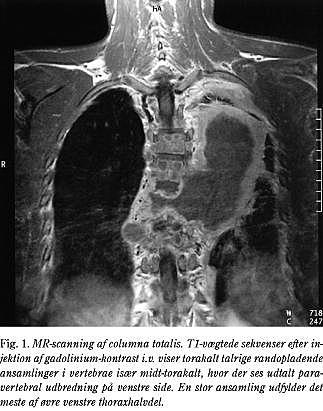

MR-scanning viste svært torakalt sammenfald over fire niveauer med stor paravertebral abscesdannelse og absces i rygmuskulaturen (Fig. 1). Ligeledes svær involvering af L5 med spinalstenose. Klinisk fandtes spastisk paraparese med fodklonus, hyperaktive reflekser, øget tonus samt nedsat kraft over knæ, hofter og fodled. Der blev foretaget primær dekompression og indlagt dræn.